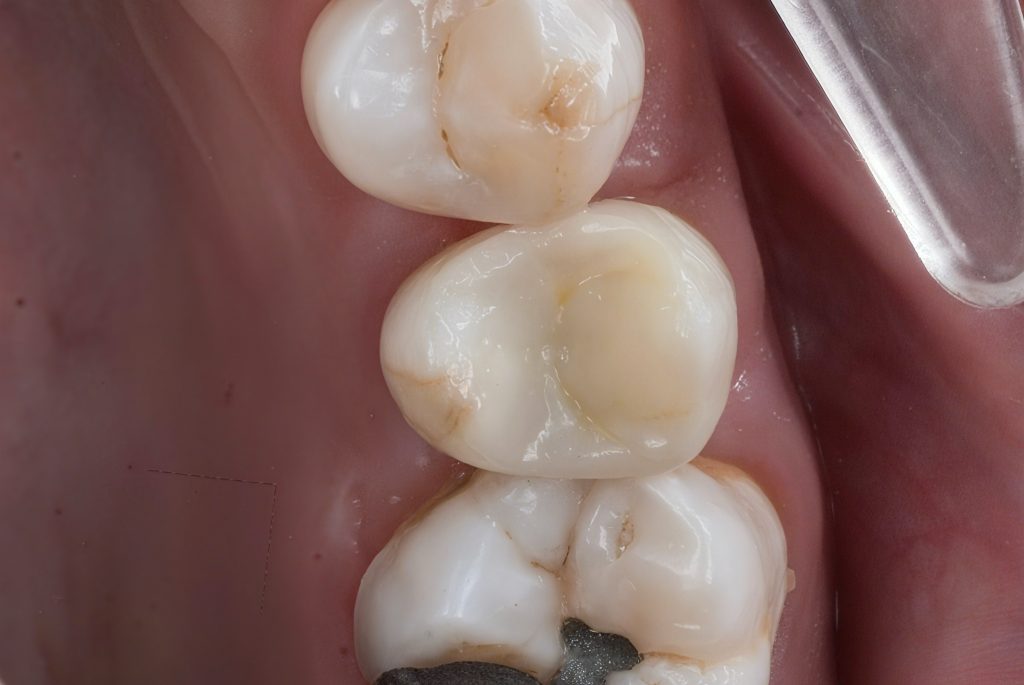

Clinical and radiographic exam confirmed adjacent Class II carious lesions affecting both teeth, with secondary caries beneath existing composite and defective margins.

Rubber dam isolation achieved using clamp stabilization to maintain a dry and clean operative field – essential for adhesive dentistry (Fig 1–2).

- Preoperative occlusal view showing defective composite & caries

- Rubber dam isolation